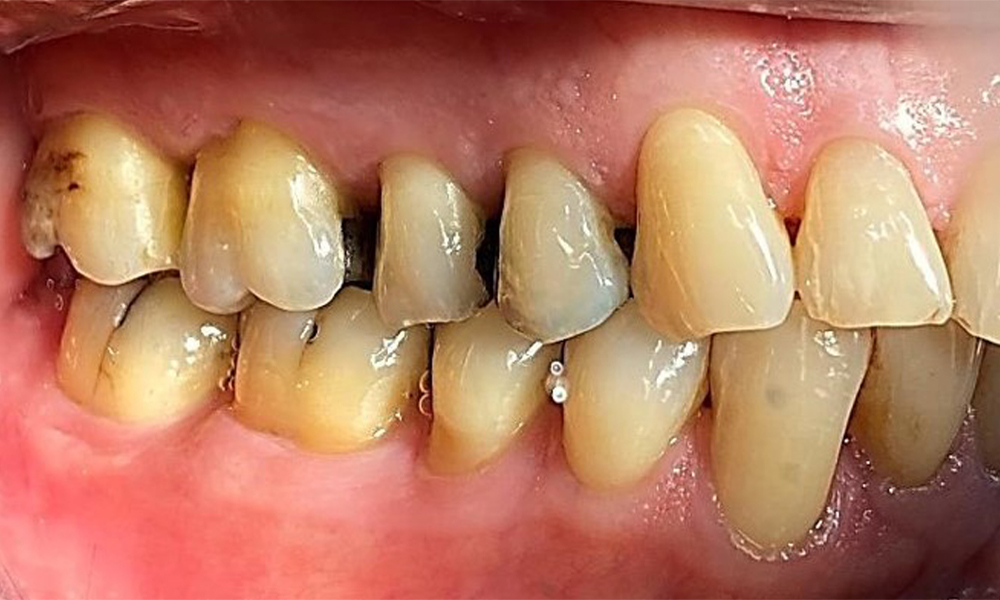

Зъбни резултати

Пациентът има пълно съзъбие с 28 зъба, което включва амалгамни и композитни пломби в областта на моларите и премоларите. На зъб 14 има видима клинична маргинална празнина. Зъб 27 има адекватна златна инкрустация. Налице са и генерализирани атриции и абразии. (фиг. 2, фиг. 3, фиг. 4, фиг. 5, фиг. 6)

Пародонтални резултати

Пациентът е с пародонтит II стадий, степен В (5). Клиничните дълбочини на сондиране от 1 до 3 mm са във физиологичния диапазон. Локализирани дълбочини на сондиране от 5 mm са наблюдавани медиопалатинално на 17 и 27. Налице са генерализирани рецесии от 1 до 3 mm с частична загуба на интердентални папили (фиг. 2, фиг. 3, фиг. 4)